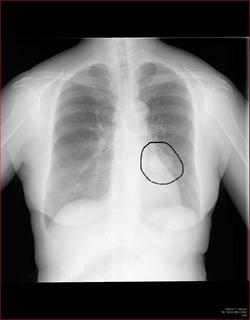

わかりにくいかもしれませんが、このあたり。

気管が追いにくい、無くなっているようにも見えます。

気管狭窄ですね。こういう所見もレントゲンで捉えることができるのです。